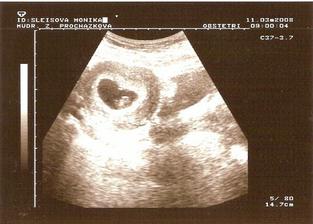

11.3.2008- viděn plod, už i se SRDÍČKEM :O)